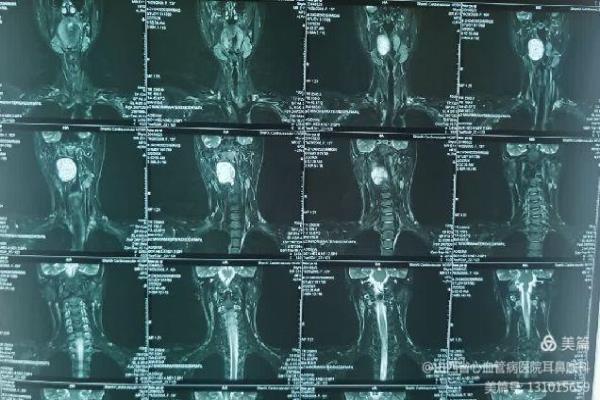

患儿就诊时,自觉偶有憋气及咽痛。张浩杰主任第一时间接诊,经过仔细查体、喉镜和颈部影像学CT与MRI检查后,发现患儿咽腔明显受压,口咽部椎前间隙巨大肿瘤。

该例肿瘤生长部位特殊,位于咽部椎前间隙,周围神经血管丰富,手术风险较大。然而,如果不及时治疗,肿瘤会继续增大,压迫周围组织,导致呼吸困难、吞咽困难等症状,严重时甚至危及生命。